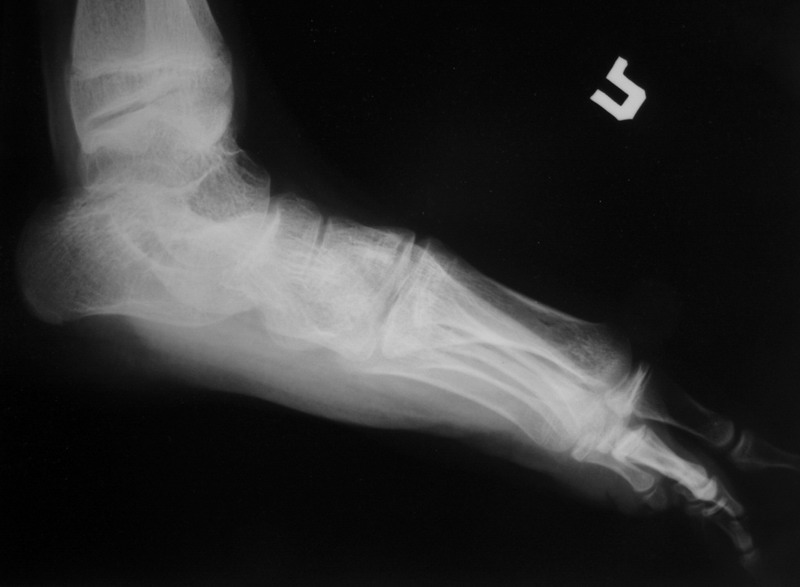

Пациент 15 л., болезнь Литтля, спастический нижний парапарез, интеллект высокий. Ребенок настроен на активный образ жизни. С недавнего времени начал ходить без дополнительной опоры. Появилась проблема с левой стопой - во время ходьбы опора приходится на смещенную кнутри таранную кость.

Может образоваться болезненный натоптыш или язва.Общепринятой операцией является трехсуставной артроде с мобилизацией таранной кости. Выполнять такую операцию у спастика и в раннем возрасте проблематично. Родстьвенники тем более готовы материально и морально осуществить хирургическое лечение за рубежом, если оно показано и возможно.Предпочтительно в Австрии и Германии. Если кто-то посоветует координаты таких клиник - были бы признательны.

Это типичная проблема со стопами у больных спастическим церебральным параличом. У Вашего пациента ситуация несколько запущена. Но решать её надо.

Стандартным хирургическим вмешательством в таком случае действительно является костнопластический корригирующий трёхсуставной артродез, вероятно с мягкотканным компонентом (эквинус). Такие операции без риска нарушения роста стопы можно выполнять с 12-летнего возраста. Так, что у Вашего пациента никакой опасности нет. Делать это можно где угодно по желанию родителей. Но, может быть не кидаться сразу за границу. У нас специалисты не хуже (а, может быть и лучше). Это и институт Турнера под С-Пб, и 18-я неврологическая больница в Москве (А.М.Журавлёв). Делаем такие операции и мы. Важный момент: после операции необходим полноценный специальный курс реабилитационного лечения, ортопедические пособия и наблюдение.

В приводимом случае, 15 летнему больному показан 3-суставной артродез. Однако считаю нецелесообразным существенно менять конфигурацию стопы, поскольку плоско-вальгусные деформации стоп это компенсаторный ответ на сгибательно-приводящие установки нижних конечностей. Изменение положения стоп(коррекция пронации) может нарушить сложившийся стереотип ходьбы, и ухудшить ситуацию.